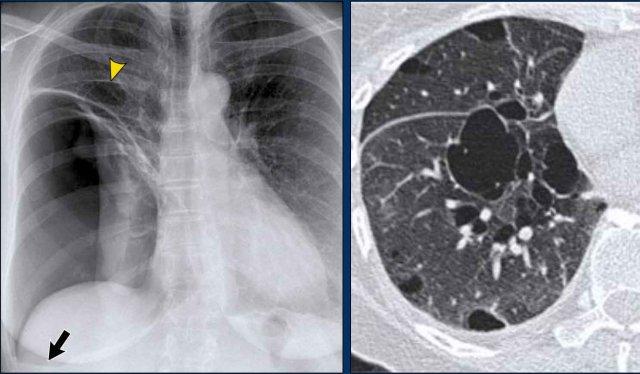

1. Không có dấu hiệu silhouette trong đám đông đặc ở thùy dưới trái (mũi tên xanh dương). 2. Dấu hiệu silhouette trong đám đông đặc ở thùy lưỡi (mũi tên vàng).

Dấu hiệu Silhouette

Dấu hiệu silhouette đề cập đến sự mất đường bờ bình thường giữa các cấu trúc có tỷ trọng X-quang khác nhau, thường gặp nhất là phổi chứa khí tiếp giáp với các cấu trúc phần mềm như tim hoặc cơ hoành.

Dấu hiệu này có vai trò quan trọng trong việc phát hiện các tổn thương kín đáo và định khu tổn thương trong lồng ngực.

Minh họa Dấu hiệu Silhouette

- Không có Dấu hiệu Silhouette (Mũi tên Xanh dương)

- Tâm thất trái, nằm ở phía trước, bình thường được tiếp giáp với thùy lưỡi chứa khí của thùy trên trái.

- Nếu đông đặc xảy ra ở thùy dưới trái (phía sau), ranh giới giữa thùy lưỡi và tim vẫn còn nguyên vẹn, và bờ tim trái được bảo tồn.

- Dấu hiệu Silhouette Dương tính (Mũi tên Vàng)

- Khi đông đặc hiện diện ở thùy lưỡi, vùng này tiếp giáp trực tiếp với bờ tim trái, làm mờ bóng của tâm thất trái.

- Điều này cho thấy tổn thương nằm ở phía trước lồng ngực.

Dấu hiệu Silhouette – Các Ví dụ

Ca lâm sàng 1: Tư thế PA

- Bờ tim trái bị xóa mờ trên phim X-quang tư thế PA.

- Ngay cả khi chưa xem phim nghiêng, dấu hiệu này đã định khu tổn thương ở phân thùy trước của phổi trái, nhiều khả năng là thùy lưỡi.

- Chẩn đoán: Viêm phổi thùy do Streptococcus pneumoniae.

Ca lâm sàng 2: Tư thế PA

- Quan sát thấy đám đông đặc ở thùy dưới trái (mũi tên vàng).

- Bờ tim trái vẫn được xác định rõ với bóng silhouette bình thường (mũi tên xanh dương), cho thấy tổn thương nằm ở phía sau và không liên quan đến thùy lưỡi.